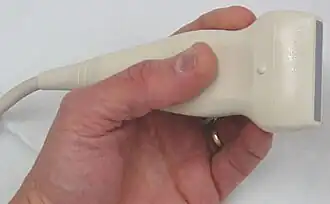

Produção da onda sonora

A Ultrassom é tipicamente produzido utilizando um transdutor piezoelétrico. O transdutor é o componente do aparelho de ultrassonografia que entra em contato com o paciente e é conectado ao restante do equipamento através de um cabo.

Um material piezoelétrico converte uma tensão (ou pressão) em um campo elétrico, e vice versa. Transdutores usados para imageamento utilizam cerâmica piezoelétrica sintética, normalmente titanato zirconato de chumbo (PZT).

Uma voltagem oscilando com alta frequência aplicada através do material piezoelétrico cria uma onda sonora com a mesma frequência. Uma pressão oscilante aplicada a um material piezoelétrico cria uma voltagem oscilando através dele. A medida dessa voltagem fornece uma maneira de registrar ondas ultrassônicas. O mesmo material piezoelétrico pode funcionar tanto como fonte quanto como detector!

O som é direcionado pelo formato do transdutor ou por sistemas mais complexos de controle. Há um intervalo de alguns milissegundos entre a produção de cada pulso de ondas ultrassônicas. Durante esses intervalos, há a captação das ondas que são refletidas.

A direção do feixe é rapidamente alterada para cobrir uma região do corpo em forma de leque. Isso pode ser feito com um arranjo de transdutores que são pulsados sequencialmente, ou com um arranjo faseado de transdutores que são pulsados juntos.